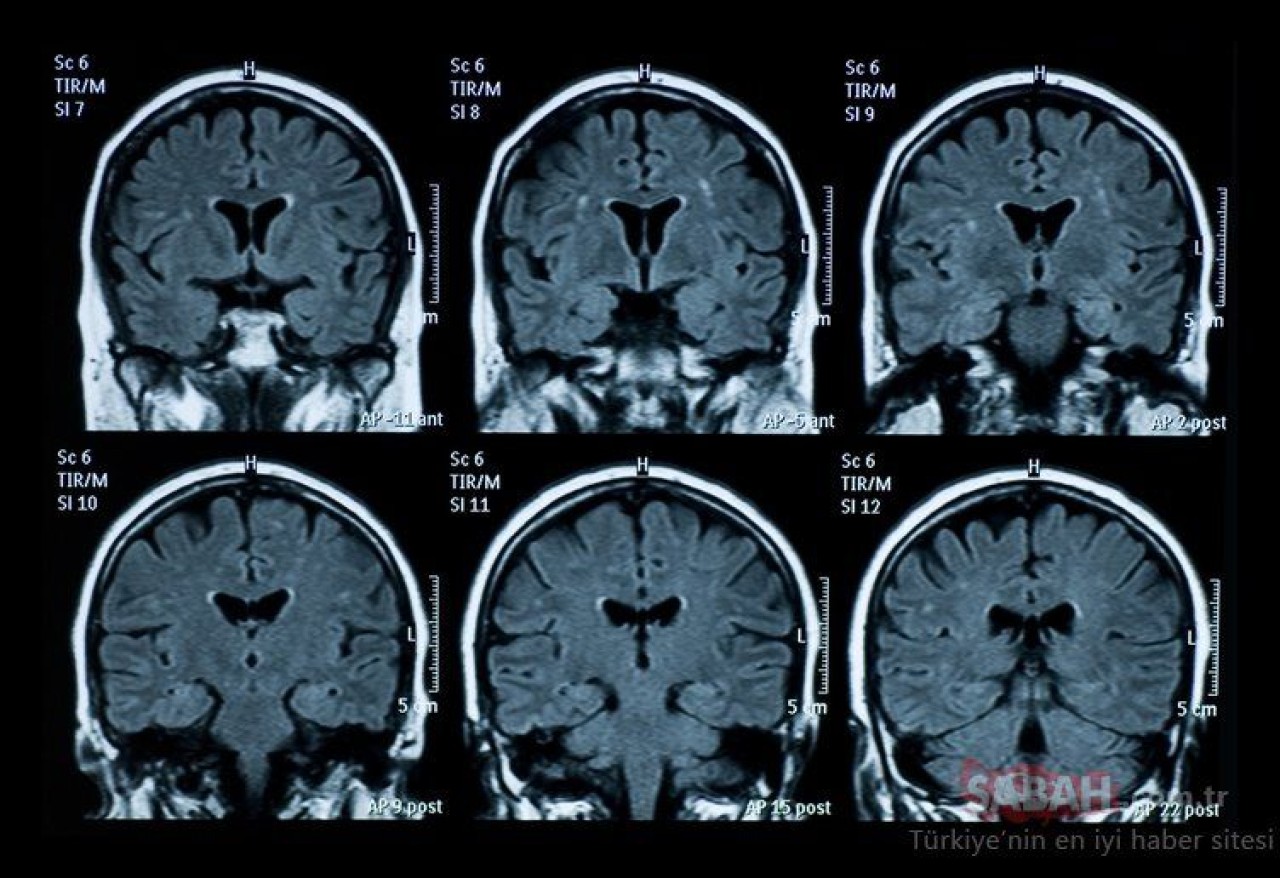

Bu durum, sinir sistemi ve beyinde ciddi ve kalıcı hasara yol açabilir. Tedavi edilmeyen ve ciddi boyuta ulaşana kadar fark edilmeyen B12 vitamini eksikliği kişide derin depresyona, paranoya ve sanrılara, hafıza kaybına, idrar kaçırma ile tat ve koku kaybına dahi yol açabilmektedir.

B12 vitamini eksikliği tedavi edilmezse, ciddi nörolojik sorunlara ve kan hastalıklarına yol açabilir